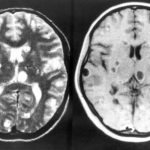

Médicos encuentran larvas en el cerebro de un joven de 18 años

Médicos indios descubrieron el cerebro de un joven de 18 años plagado de quistes causados por un parásito porcino. El muchacho, al que los...